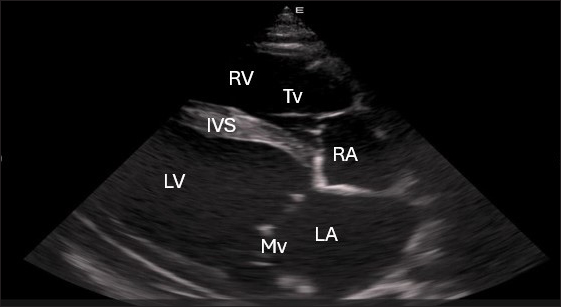

Left parasternal ultrasonography

Figure 5 shows an image of the ventricles, atria, and interventricular septum in the caudal long-axis four-chamber view acquired by positioning the probe perpendicularly in the fourth intercostal space or longitudinally in the fifth intercostal space with a little clockwise rotation. Every camel had a perfectly normal heart anatomy, including ventricles, tricuspid valve, mitral valve, and atria on both sides. During the fourth ICS image of the LVOT, the probe was turned slightly further cranially and twisted somewhat counterclockwise (Fig. 6). No camel is complete without an oblique aortic cross-section.

Fig. 5. Left parasternal longitudinal axis (Systole) of 16 years racing camel showing Lv=left ventricle, Rv=right ventricle, Ivs=interventricular septum, Mv=mitral valve, and Tv=tricuspid valve.